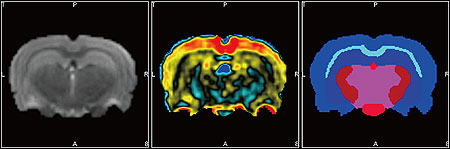

BrainAtlas プラグイン (マウス・ラット用)

BrainAtlasプラグインモジュールを利用することにより、イメージング画像の 脳アトラス・マッピングを、簡便且つ迅速に行うことができます。

プラグインには、マウス・ラットの脳アトラスがライブラリとして予め組込まれています。このライブラリを利用することによって、ROIを手作業でひとつひとつ設定する必要なく、CTまたはMRI画像と脳アトラスの位置合わせを行うことができ、解析作業の生産性が向上します。マップと実像がずれてしまう場合にも、マニュアルによる調整を行なうことができます。

ライブラリに予め組込まれた脳アトラス

• マウス用アトラス:14領域

• ラット用アトラス:54領域

• 全脳、もしくは左右大脳半球に適用可能

• 各部位のVoxel定量化が可能

• 定量データのCSVエクスポートが可能:

各ROIのVoxelサイズ・容積と共に、

モダリティに合わせた定量値(CT値・放射線量等)が、

統計学的に出力されます。

BrainAtlas プラグイン

自動分類されたROI一覧

BrainAtlas 適用前(左)・後(右)の画像